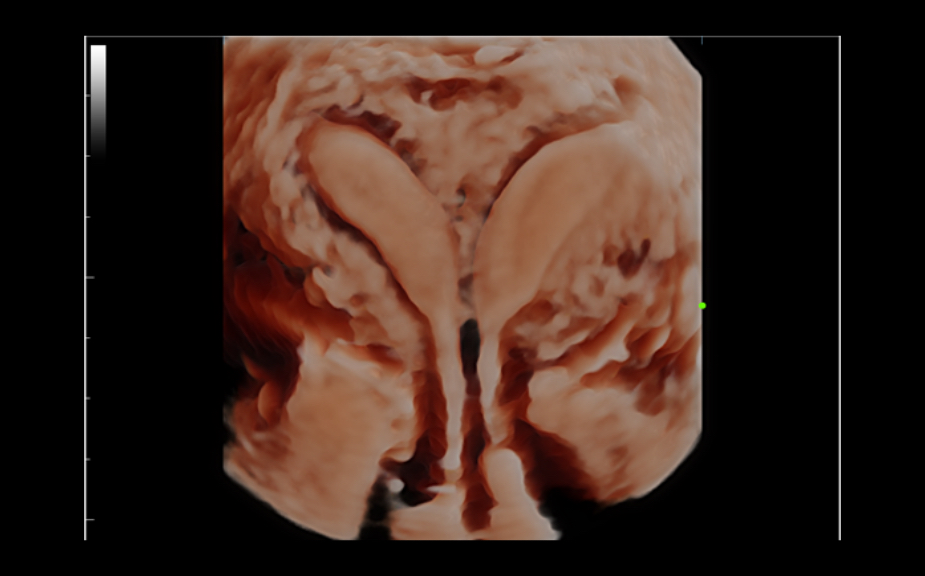

ImĂĄgenes clĂnicas